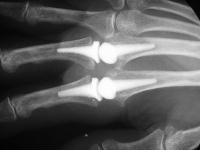

and after implant placement.

Click for larger image

Pre and postop radiographs.